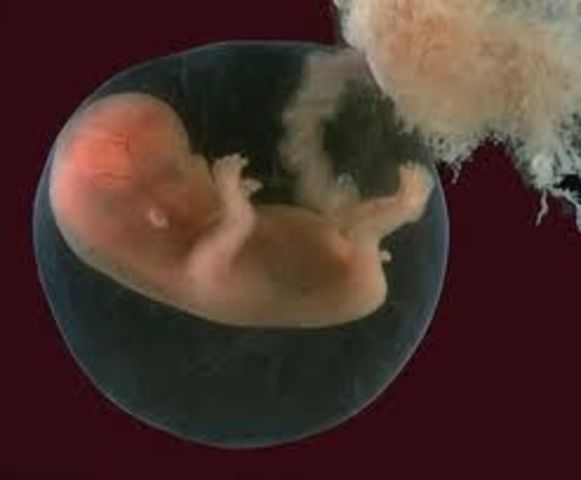

El embrión empieza a desarrollar los vestigios de los futuros órganos y aparatos.El cambio más importante que se produce es el plegamiento del disco embrionario: la notocorda es el diámetro axial de un disco que comienza a cerrarse sobre sí mismo, dando lugar a una estructura tridimensional seudocilíndrica que empieza a adoptar la forma de un organismo vertebrado